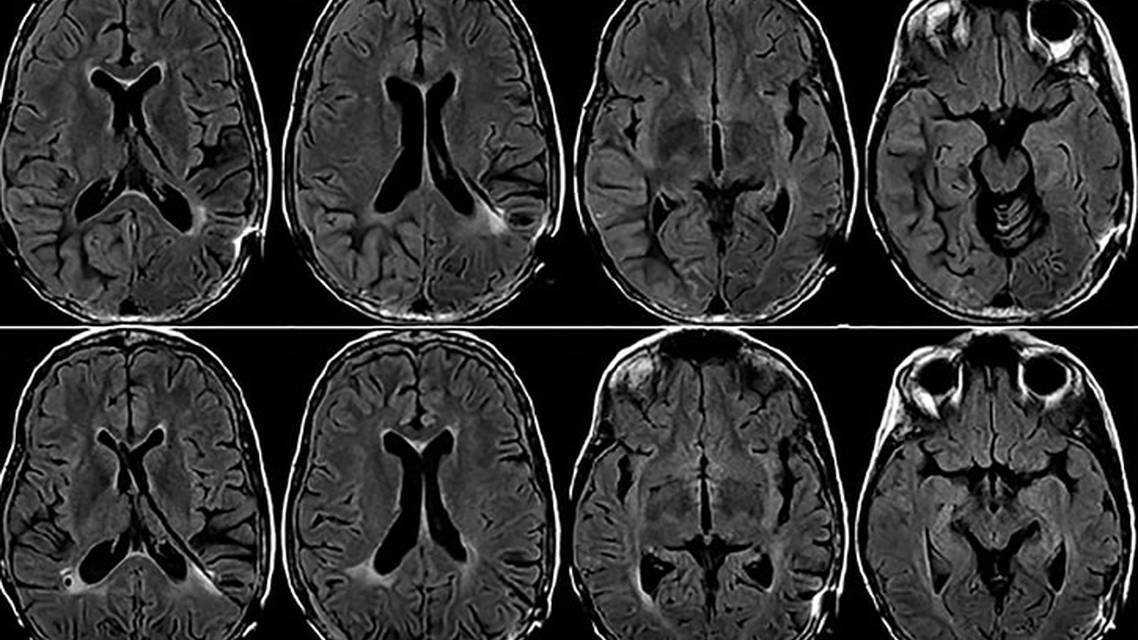

Ms A’s continued visual deficits, motor weakness, and gait difficulties were concerning for persistent focal seizures. Her brain MRI demonstrated diffuse cortical thickening, enhancement, and T2/fluid-attenuated inversion recovery (FLAIR) hyperintensity involving her right temporal, parietal, and occipital lobes (Figure). These MRI findings suggested Ms A was experiencing focal seizures secondary to right-sided cortical enhancement. Continuous EEG monitoring in the inpatient setting did not show any seizure activity, however. CT neck angiography revealed multifocal moderate-to-severe stenosis in both vertebral arteries, specifically at the foramen magnum, distal cavernous right internal carotid artery, and the A2 segment of the right anterior cerebral artery. Cerebrospinal fluid (CSF) analysis results were largely unremarkable except for elevated protein at 274 mg/dL and red blood cells at 393 per mm3 (Table 1). Results of a comprehensive metabolic panel, complete blood count, and inflammatory markers (lactate and erythrocyte sedimentation rate) were within normal limits.